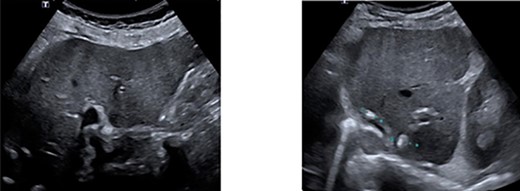

One year after surgery, his right testis was swollen and painful. There was no dysuria or hematuria. On scrotal examination, a small nodule (approximately 1 cm in diameter) was felt in his right testis. Ultrasonography showed a hydrocele of the right testis with thickening of the scrotal wall and a tumorous mass (Fig. 4). An orchiectomy was performed and pathologic analyses revealed a metastasis of the adenocarcinoma between tunica albuginea and tunica vaginalis. He started palliative chemotherapy containing capecitabine and bevacizumab. The CT scan after three cycles of chemotherapy showed a partial remission.

Ultrasonography of right testis showing hydrocele and a tumorous mass.